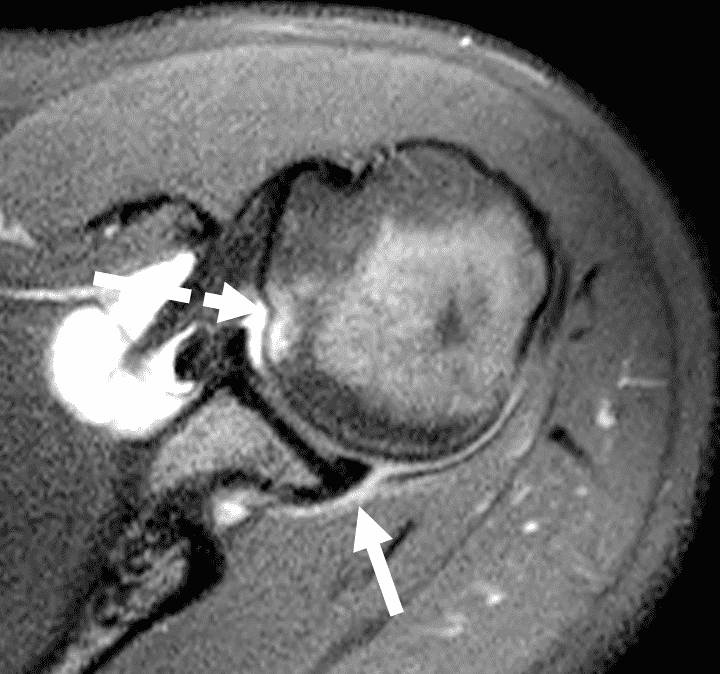

20 year old right-handed hitting college baseball player with left shoulder injury. Fat-suppressed proton-density-weighted axial images at the mid (1A) and inferior (1B) left glenohumeral joint are provided. What are the findings? What is your diagnosis?

Figure 2: The axial images (2A and 2B) demonstrate findings of a posterior glenohumeral instability injury including posterior to posteroinferior capsulolabral tearing and pericapsular edema (solid arrows) and an anteromedial humeral head impaction injury (dashed arrows).